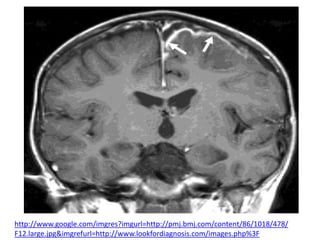

DIAGNÓSTICO

La RNM y la TAC con contraste son los

métodos diagnósticos de

elección, permitiendo además la detección de

un foco parameníngeo responsable y de

complicaciones asociadas.

En la TAC sin contraste, el empiema suele manifestarse como

un área hipodensa sobre un hemisferio o a lo largo de la hoz

cerebral

La RNM proporciona mejores datos que la TAC en relación con la

naturaleza y extensión del empiema subdural.

El empleo de gadolinio como medio de contraste aumenta la

sensibilidad de esta técnica.

http://www.google.com/imgres?imgurl=http://pmj.bmj.com/content/86/1018/478/

F12.large.jpg&imgrefurl=http://www.lookfordiagnosis.com/images.php%3F